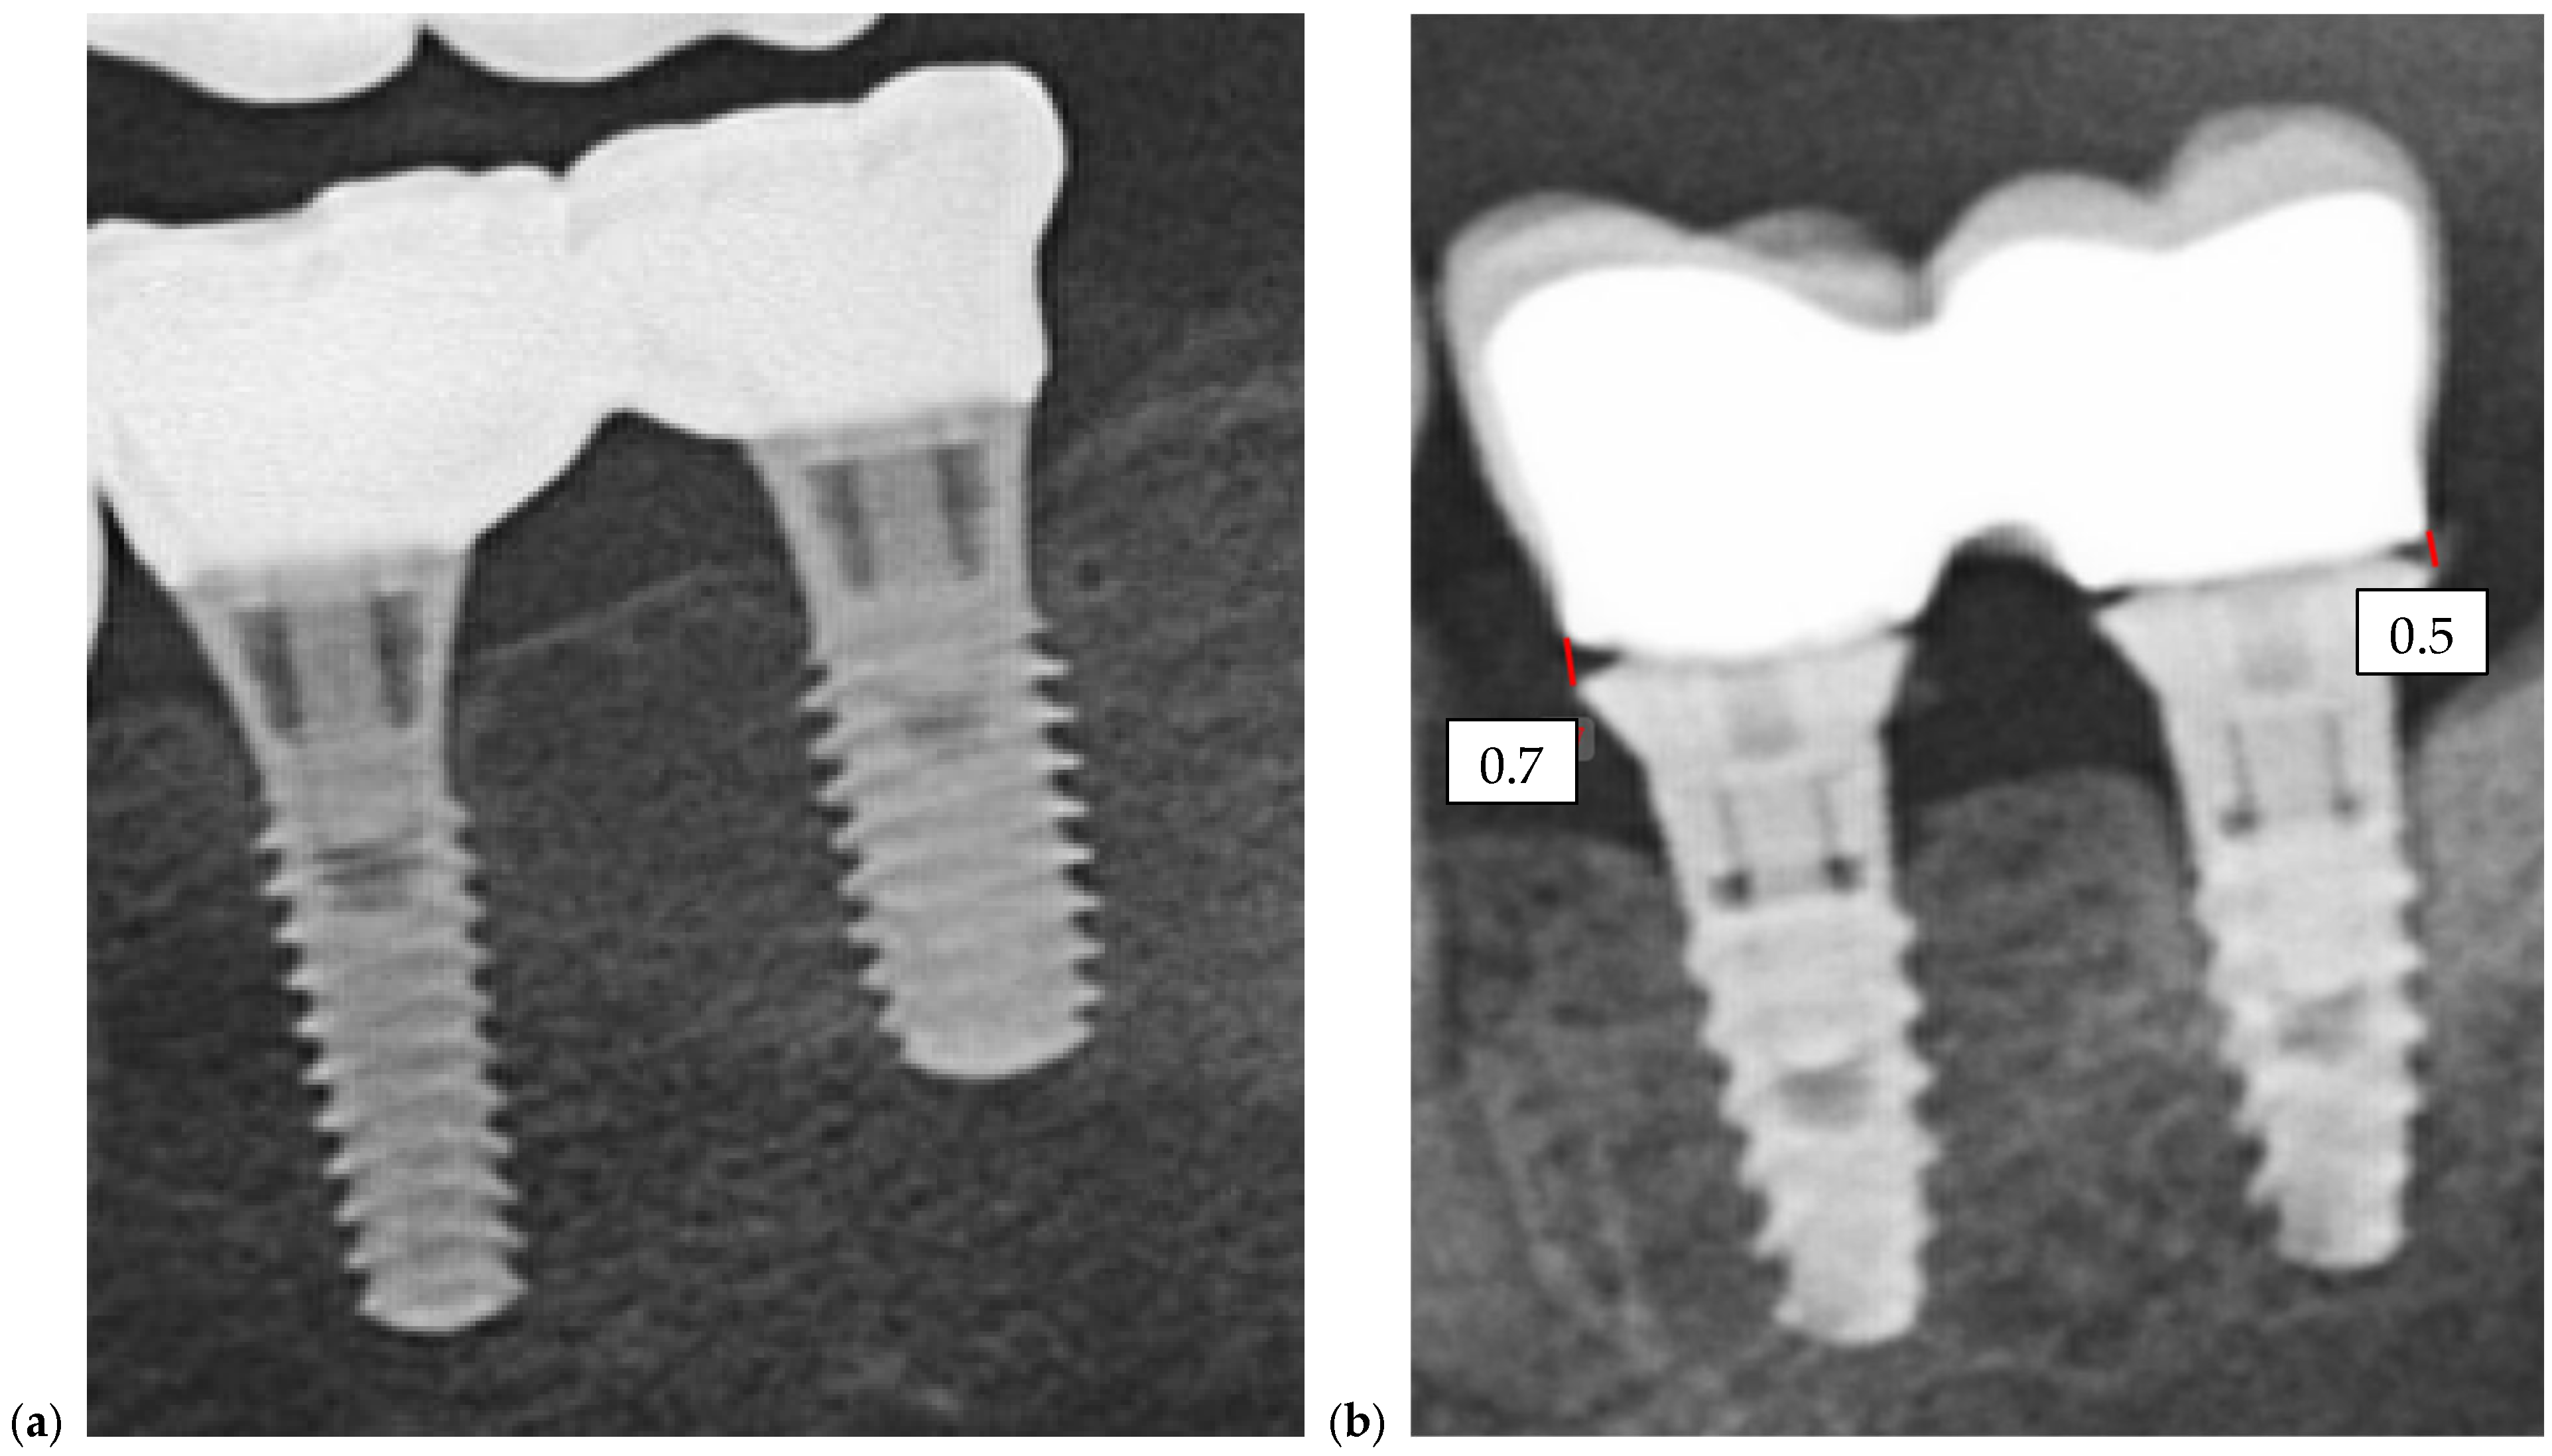

Radiographic assessments were conducted during the initial impression phase, provisional restoration try-in, and final prosthesis delivery. CBCT, panoramic radiographs, and intraoral periapical radiographs were used to visualize the implant–abutment interface and prosthetic fit. All imaging was performed using standardized exposure parameters, with radiographs analyzed using calibrated digital imaging software to assess marginal gaps and seating accuracy. In Figure 6, a representative case is presented, illustrating the radiographic sequence from the patient’s initial visit to the annual follow-up appointments. Figure 6a shows the panoramic radiograph (OPG) obtained at the first visit. Figure 6b corresponds to the postoperative image taken immediately after implant placement. Figure 6c illustrates the situation six months after surgery, following the delivery of the temporary restoration. Figure 6d shows the radiograph taken six months after provisional restoration was delivered, immediately after delivery of the definitive restorations. Figure 6e–i represent the annual recall examinations. Vertical marginal discrepancies were quantified as linear distances in millimeters (mm) at the implant–abutment interface. All radiographic examinations (periapical, panoramic, or CBCT) included in the analysis were obtained strictly for clinical diagnostic and follow-up purposes according to standard treatment protocols. No supplementary exposures were performed for research reasons. Data were analyzed retrospectively from existing clinical records. Impression procedure duration was recorded in minutes (min). Patient-reported outcomes were collected as Visual Analog Scale (VAS) scores on a 1–10 scale (dimensionless) (Appendix A). The same diagnostic criteria were applied across both digital and conventional groups to ensure consistency.

Figure 6. Representative panoramic radiographs obtained at different clinical stages of treatment. All radiographs were part of standard patient follow-up and were retrospectively analyzed; no additional exposures were performed for research purposes. (a) initial panoramic radiograph at the first visit; (b) postoperative image following implant placement; (c) six-month follow-up after surgery, at delivery of the temporary restoration; (d) radiograph taken six months after temporary restoration, immediately after delivery of the definitive restorations; (ei) annual recall examinations demonstrating stable peri-implant bone levels over time.